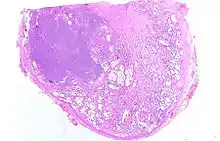

Adénocarcinome prostatique

Adénocarcinome ; tissus indifférenciés

Invasion périneurale par un adénocarcinome prostatique. HE, x400